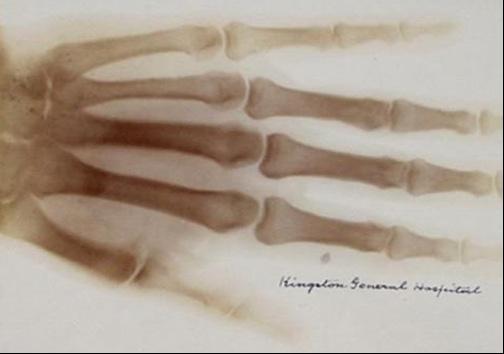

By the turn of the century, more than 1,000 articles in X-rays were published worldwide. The first X-ray taken in North America was produced at Davidson College in North Carolina on January 12th, 1896. The first diagnostic X-ray photograph in North America was taken on February 3rd, 1896, at Dartmouth College in New Hampshire. Soon after, on February 17th, 1896, a radiograph was taken of Victorian singer Madame Emma Albani at the Royal Military College in Kingston, Ontario (fig. 3). Kingston General Hospital secured its place as one of the first in North America to obtain an X-ray machine for routine clinical work in the fall of 1896.

With jittering excitement, Roentgen began attempting to stop the rays by placing various objects around his laboratory between the cathode tube and the screen: a book, different metals, and eventually his own hand. He saw shadows of his bones. He noted the varying penetration of the X-rays through materials. A few weeks after his initial discovery, he used his crude X-ray machine to photograph his wife Anna Bertha’s hand. “I have seen my death!” Anna exclaimed as she viewed the picture— the first radiograph (fig. 2). The famous image of Anna’s hand with the outline of her wedding ring has since been immortalized in medical history.

Professor Roentgen announced his discovery at the Würzburg Physico-Medical Society meeting in December 1895. His original paper was published on December 28th, 1895. Within the first few weeks following Roentgen’s announcement, X-ray photographs were used in Berlin to examine the results of recent surgical work, with before and after radiographs of the new fractures and then surgically repaired fractures. In Vienna, embedded bullets were being photographed with X-rays, instead of being surgically probed for, and subsequently removed with comparative ease. Radiography's life-saving capabilities then made international headlines with a story out of London. A sailor was brought to the hospital wounded and barely responsive from an unidentified injury. They discovered an object embedded in the spine using X-rays, which turned out to be a small fragment of a knife blade after it was successfully removed. The sailor lived thanks to the recently discovered X-ray machinery, and likely moreso thanks to the tetanus antiserum coincidentally discovered five years earlier.

Roentgen’s legacy constitutes one of the most significant discoveries in the field of medicine that ignited exponential change in healthcare. From modest beginnings of incidental discoveries, radiology has become a cornerstone of modern medicine, blossoming into an integral role in the patient care continuum. From the radiograph exhibiting Anna Bertha’s wedding ring, to the clarity of today’s imaging technologies like MRI and CT, and the future of photon counting CT and virtual reality imaging assessments, Roentgen’s observation is celebrated as leaving a magnificent legacy in medicine and the overall advancement of humanity, biology, and physics.